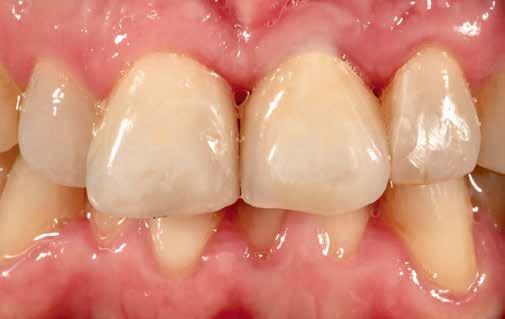

Elhagyott frontfogak, megtámadott parodoncium: a páciens kiindulási helyzete több mint nehéznek bizonyult. Yuki Momma és dr. William C. Heggerick, szerzőink, bemutatják, hogyan állítható helyre a harmónia a négy frontfog ellátásával.

A felső frontfogak állapota elhanyagolt, a parodontális struktúrák részben erősen károsodottak, VMK korona az 12 zónában, az ínyszél szürke, fekete approximális háromszögek… vörös-fehér esztétikáról nem is beszélhetünk (1. kép). Így jelentkezett a hölgypáciens a Weston Dental Specialists Group rendelőben. Elvárásai magasak voltak. A defektusok kezelését, a gingiva lefutásának korrigálását kívánta. Gyorsan világossá vált, hogy a megoldást csak a négy frontfog teljes kerámiakoronával való ellátása jelentheti. A jelen eset bemutatja, hogy az IPS e.max ZirCAD Prime segítségével hogyan lehet tiszta, tetszetős és esztétikus mosolyt létrehozni.

1. kép: Kiindulási helyzet.

oka a zománcvastagság változása cervikáltól incizál felé. A dentin, amely erőteljesebb színtelítettségű, mint a zománc, változó erősséggel tűnik át a háttérből, és tipikus karaktert kölcsönöz a fognak. Az 12-es fogon látható VMK korona (fémkerámia – a ford.) nem felelt meg ezeknek a követelményeknek, és élettelen testként tűnt fel a front megjelenésében. A 8. kép az IPS e.max ZirCAD Prime koronák próbájánál készült. Jól látható, hogy a folyamatos szín- és transzlucencia átmenet ideálisan imitálja a természetes fogakét, és plasztikus benyomást kelt. Az egyedi jellegzetességek, mint

a mamelonok és a kiemelt zománcrepedések élettelibbé teszik a koronákat.

keltett. Az egyébként ideális tipikus formájú koronák esztétikailag optimális gingivakialakítást hoznak létre, a VMK korona kicserélése egyenletes fénytovábbítást tett lehetővé a papilláktól a korona felé és fordítva is. Míg a próba során még minimális sötét approximális háromszögek láthatók voltak, a végleges beragasztásra (Variolink Esthetic, Ivoclar Vivadent) már eltűntek (9. kép). A gingiva tökéletesen hozzásimult az IPS e.max ZirCAD Prime restaurációhoz.

Összefoglalás

Anyagválasztásunk újra tökéletesnek bizonyult. Kiemelkedő természetes hatása folytán akár leplezetlen IPS e.max ZirCAD Prime anyaggal is nagyon jó esztétikai hatású monolit restaurációk készíthetők. Itt az optimális alapot képezte, hogy leplező- és festékanyagainkkal elérhessük a kívánt hatást: hibátlan mosolyt és természetes szépséget. A páciens nagyon elégedett a kezelés eredményével – akárcsak mi magunk (10. kép).